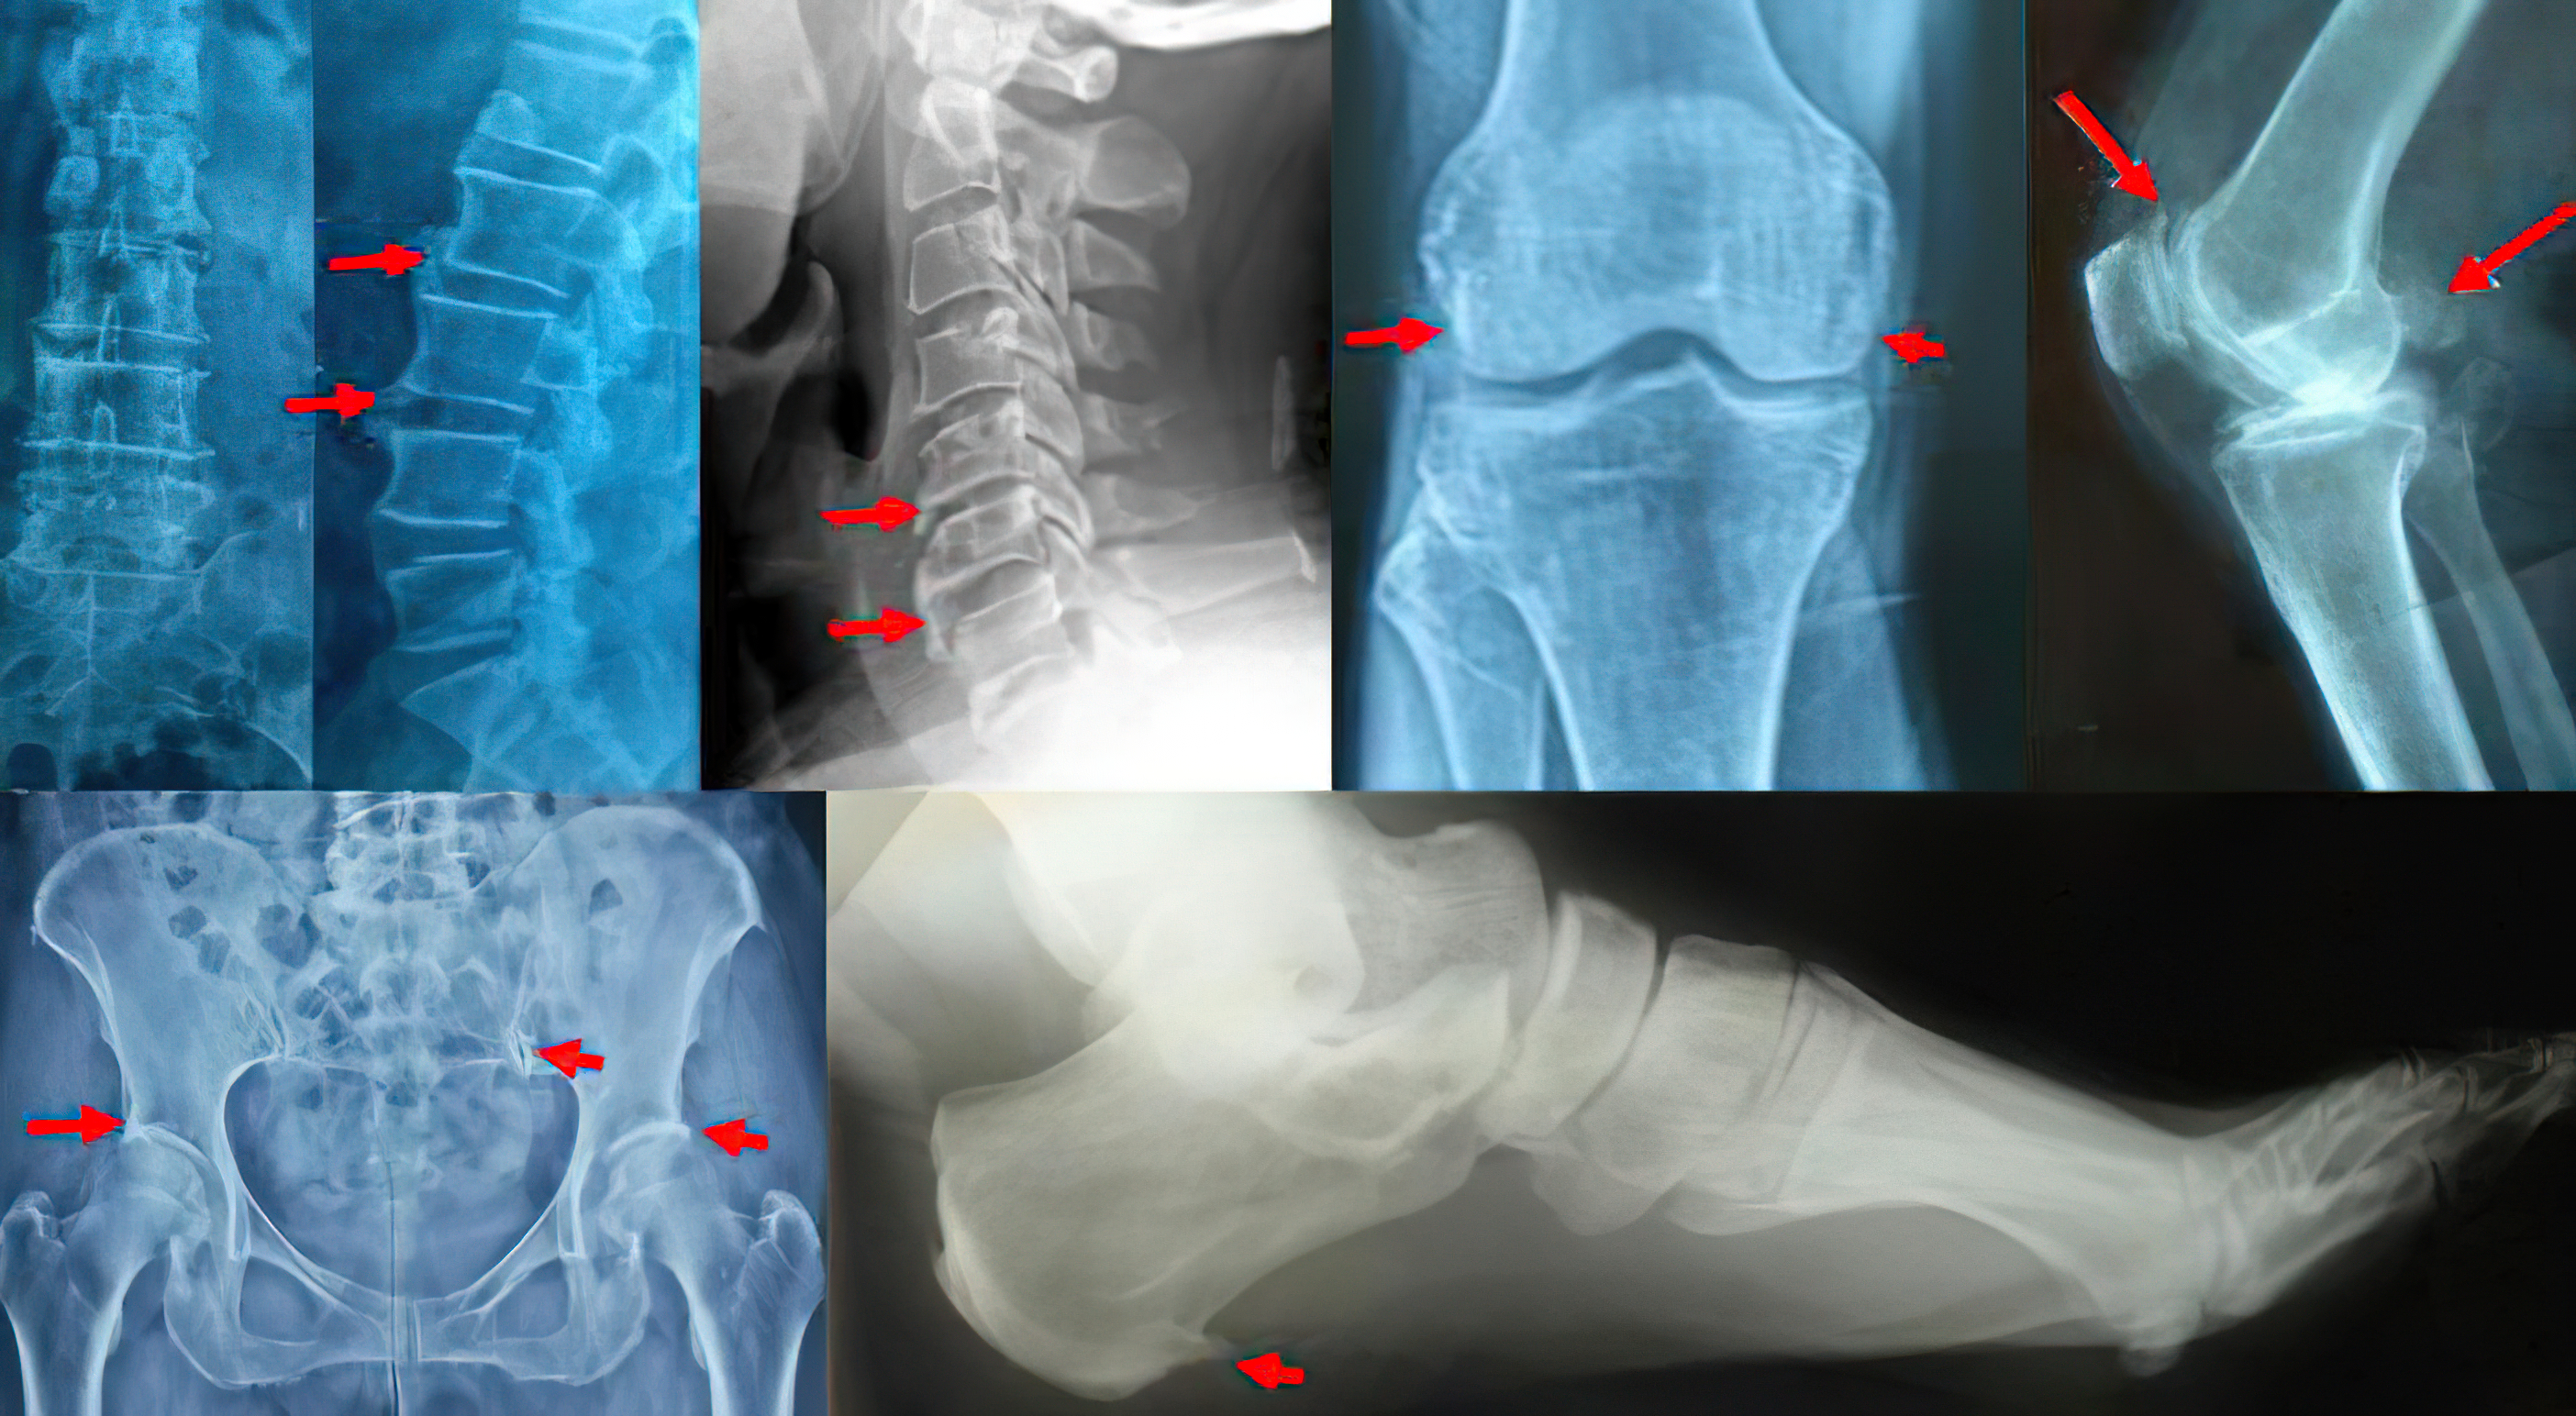

如果以整个生命周期来计算,骨刺的出现是很难完全杜绝的,骨刺是衰老的一大代言人,膝盖、腰椎、颈椎、足跟,总有地方会出现。无法避免,但我们有很多方法可以延缓骨刺的出现,以及减轻由骨刺压迫引起的症状。